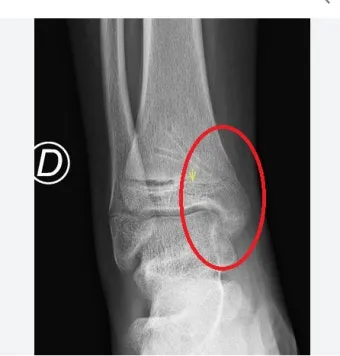

성장판은 하나의 문이 갑자기 '딱' 닫히는 것이 아닙니다. 손가락, 발가락, 손목, 발목, 골반, 척추 순으로 뼈 끝 쪽의 연골이 굳어져 가는 과정은 꽤 오랜 시간이 걸려요. 성장판의 닫히는 시기는 개인차가 매우 크답니다.

일반적으로 여성은 14-15세, 남성은 16-17세에 성장판이 닫히기 시작하지만, 완전히 닫히는 것은 만 19-20세경이에요. 하지만 여기서 중요한 건, 성장판 검사에서 '닫혔다'고 나와도 검사 오차가 있을 수 있고, 미세하게 남아있는 성장판으로 인한 성장 가능성이 남아있다는 점입니다.